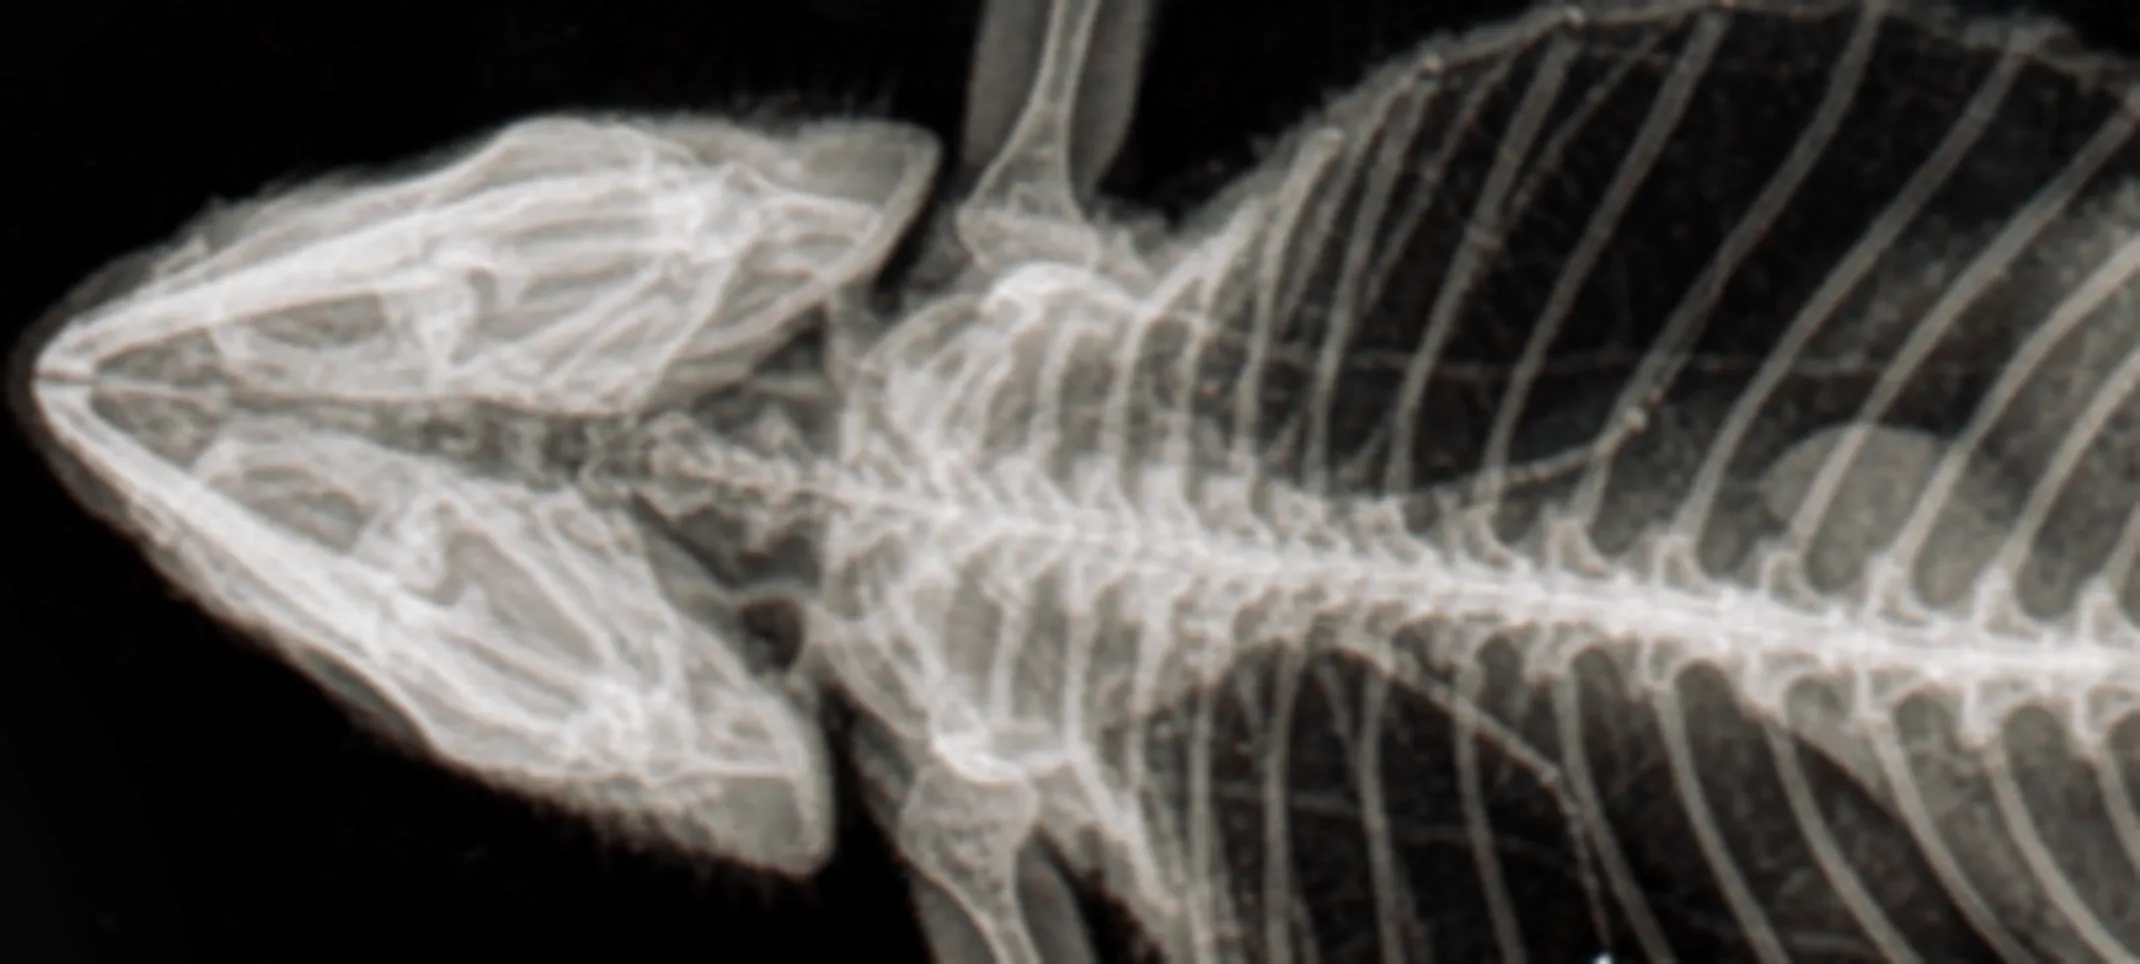

Radiography, also known as X-rays, is one of the most common and valuable medical diagnostic tools. X-rays are highly useful for screening areas of the body that have contrasting tissue densities, or when evaluating solid tissues.

X-rays can be used to detect a variety of ailments in animals including arthritis, tumors, bladder and kidney stones, and lung abnormalities such as pneumonia. They are also used to evaluate bone damage, the gastrointestinal tract, respiratory tract, genitourinary system, organ integrity, and even identify foreign objects that may have been ingested. Dental radiographs help distinguish healthy teeth from those that may need to be extracted, and identify any abnormalities beneath the gums including root damage, tumors, and abscesses. In some cases, we may need to sedate your pet or use short-acting general anesthesia.